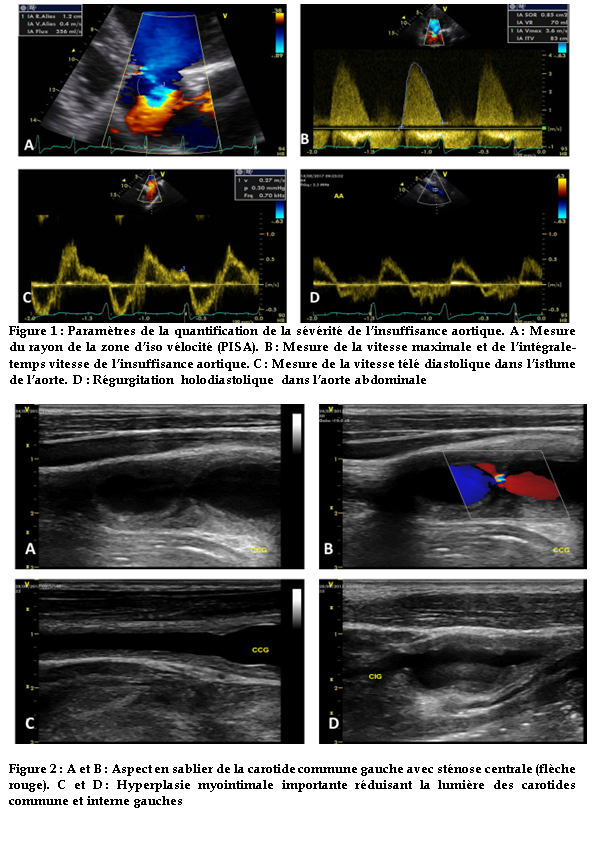

L’échocardiographie transthoracique de réévaluation objectivait une insuffisance aortique importante (VC = 8 mm ; Rayon PISA = 12 mm ; Surface de l’Orifice Régurgitant (SOR) = 85 mm² ;Volume de régurgitation (VR) = 70 ml/battement ; vitesse télédiastolique dans l’isthme = 27 cm/s ; reflux holodiastolique dans l’aorte abdominale).

Cette régurgitation aortique était de type 3 avec un épaississement et une restriction valvulaire importante responsable d’un diastasis central. L’aorte ascendante était de taille normale.

Il y était associé une insuffisance mitrale minime de même mécanisme, une dilatation importante du ventricule gauche (42 mm/m²) avec une altération moyenne de la fonction systolique (FEVG = 30-35%) et une dilatation importante de l’oreillette gauche (VOG = 60 ml/m²). (Figure 1)

L’écho doppler des troncs supra-ortiques (figure 2) mettait en évidence un double anévrysme non thrombosé séparé par une striction de la carotide commune gauche réalisant un aspect en sablier. On notait une hyperplasie myointimale circonférentielle, régulière et bilatérale à prédominance gauche avec une lumière résiduelle de 2.5 mm intéressant les carotides communes et internes sans retentissement hémodynamique sur le lit d’aval.